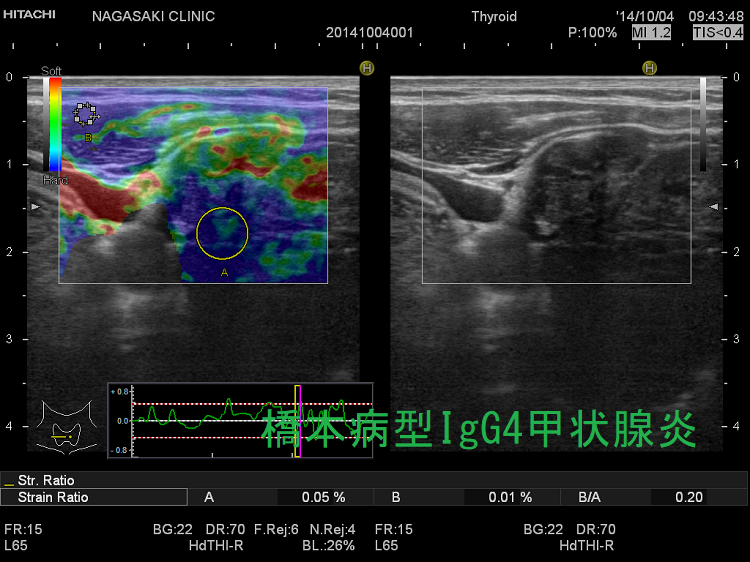

IgG4甲状腺炎(橋本病型IgG4甲状腺炎)IgG4関連甲状腺炎は、線維化が著明な白黒画像(Bモード画像)に加え、エラストグラフィーによる硬さの評価が役に立ちます。

IgG4甲状腺炎(橋本病型IgG4甲状腺炎) 超音波(エコー)画像

橋本病型IgG4甲状腺炎 エラストグラフィー

IgG4甲状腺炎(橋本病型IgG4甲状腺炎) 超音波(エコー)画像 エラストグラフィー;線維化した部分はエラストグラフィー青く(硬く)見えます。